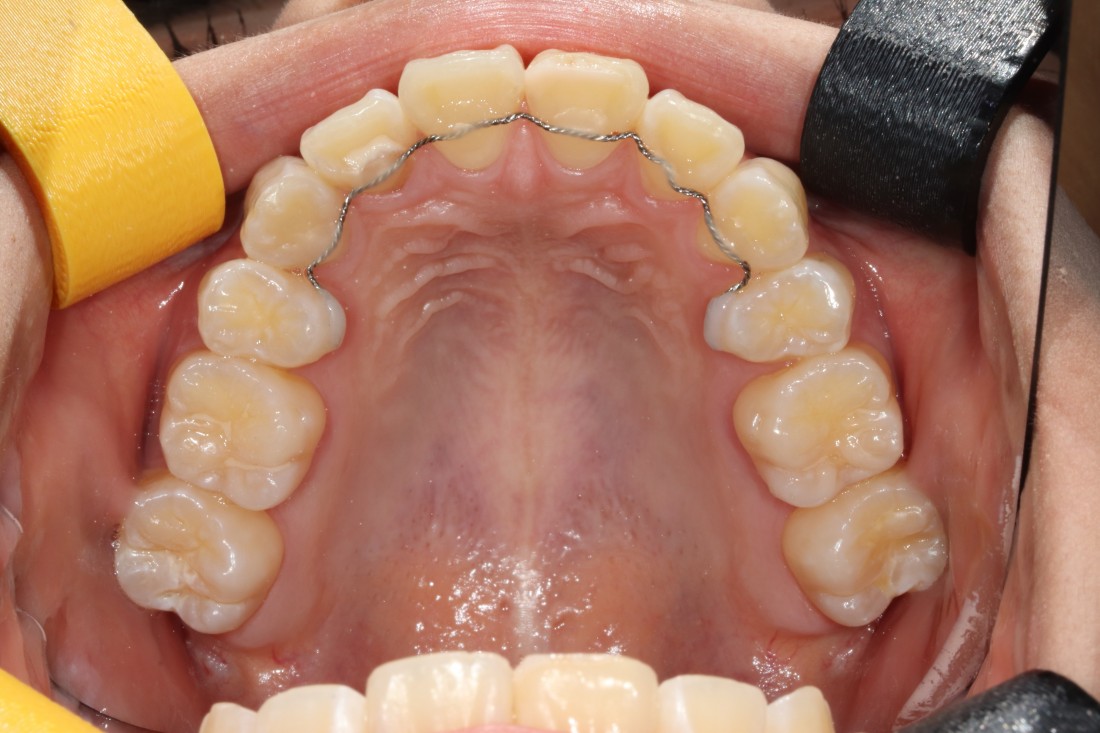

수완동 교정치과를 선택할 때는

교정전문의가 경험이 풍부한지,

교정전문의가 상담부터 진료 후 관리까지

책임지고 진료하는 곳인지

꼼꼼하게 따져보는 것이 중요합니다.

서울우리아이치과는

20년 이상 교정진료만을 담당해오신

교정전문의 대표원장님께서

교정진료의 시작부터 끝까지

1:1 책임진료를 통하여

성공적인 치아교정을 완성하고 있습니다.